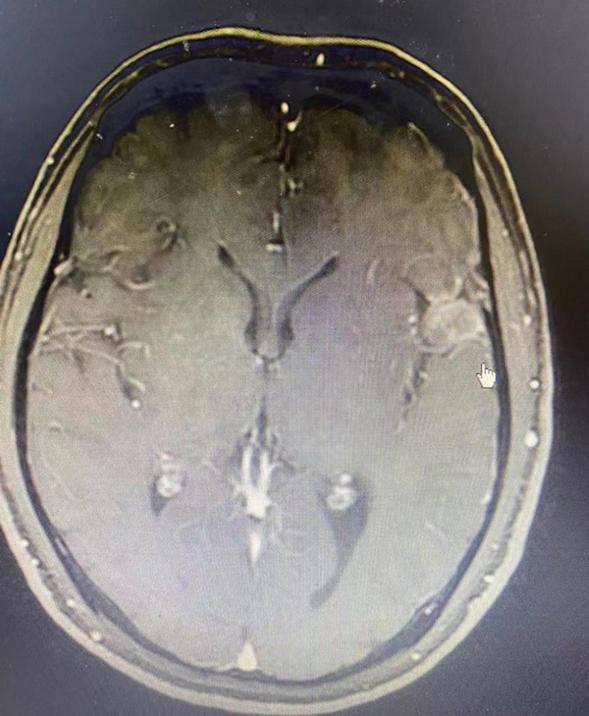

【疾病类型】星形细胞胶质瘤,WHO4级

患者35岁,2020年开春的时候,不明白原因的发生头部隐痛,钝痛,既往否认高血压史,头痛病史,并没有引起重视,直到6月底,在休息良好的状态下,自觉视物有些模糊,在医院神经内科检查,医生建议做头部CT,CT后提示颅脑内占位性病变。后患者来到我院进行了增强核磁检查,提示右侧额叶旁占位。考虑高级别胶质瘤的可能性大。患者病程还出现过眼痛,畏光现象,后在神经外科行右额叶肿瘤切除术,术后病理显示胶质细胞肿瘤,考虑为星形细胞胶质瘤,WHO 4级。术后患者出现过一次性癫痫发作,给予抗癫痫和抗惊厥治疗后症状稳定。